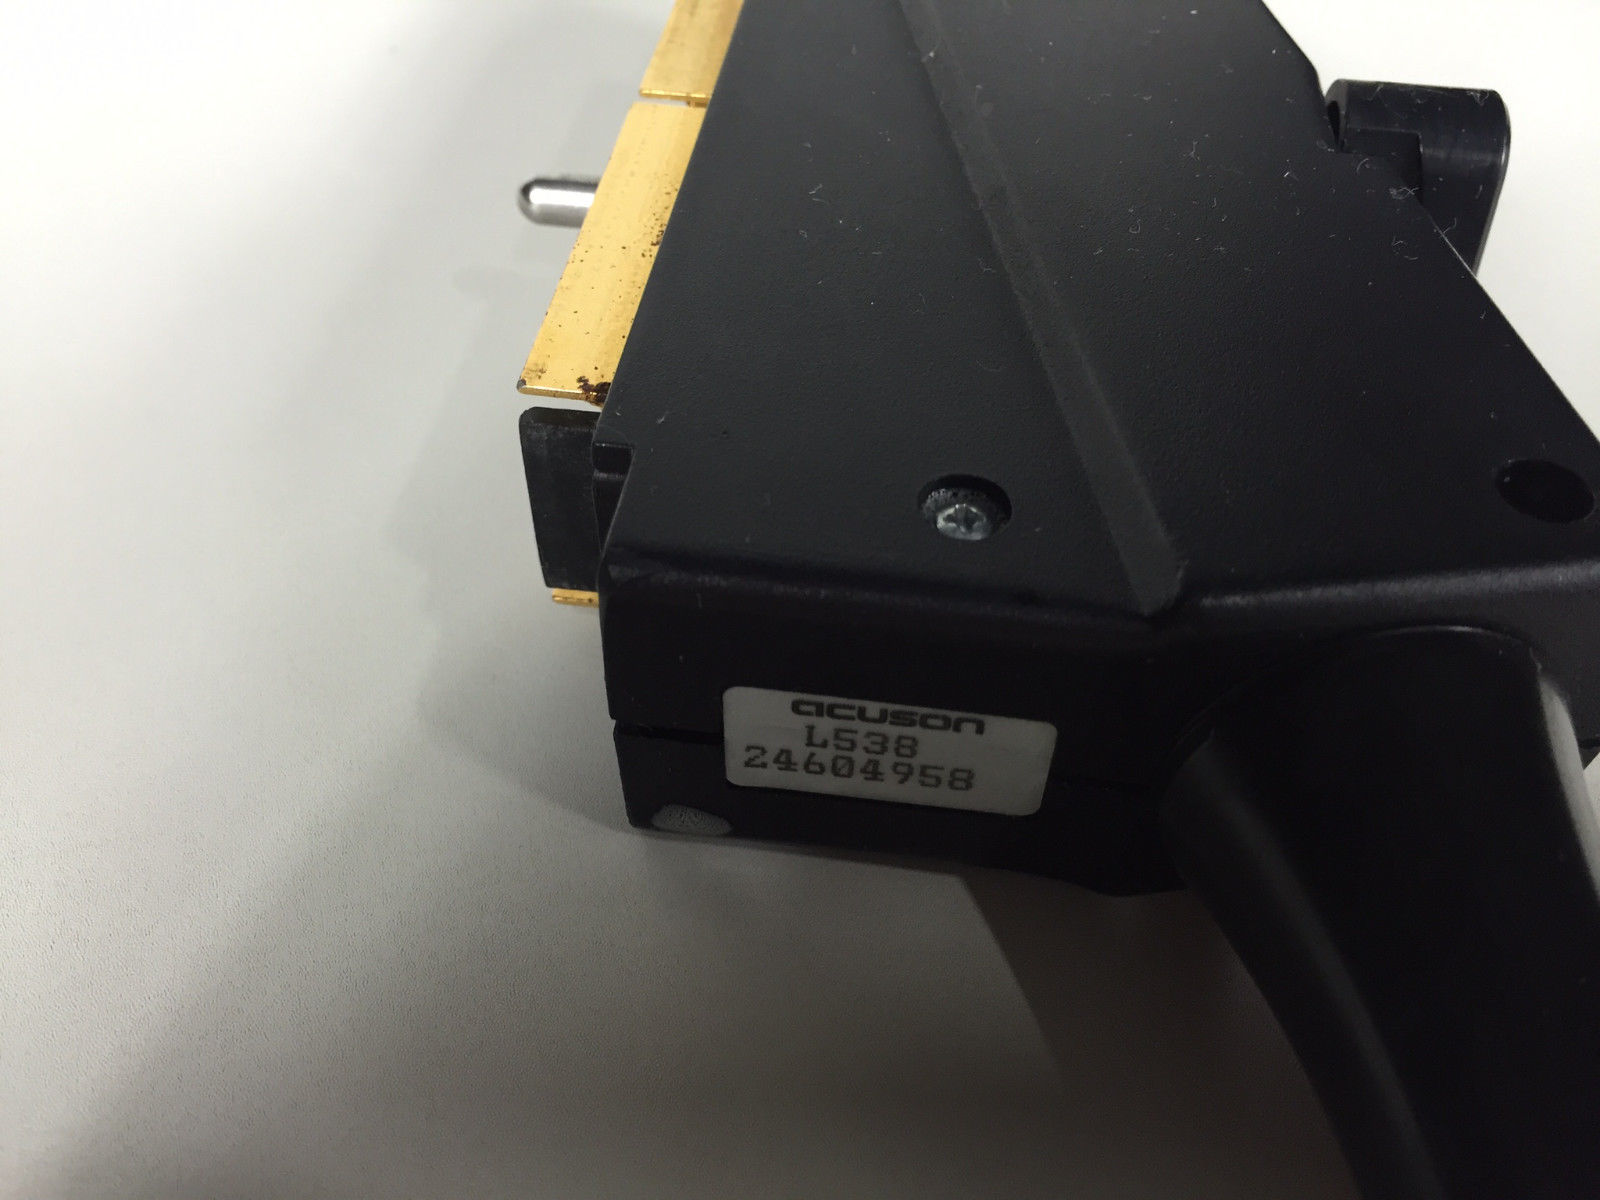

Acuson Probes

Showing 313 - 336 of 729 products